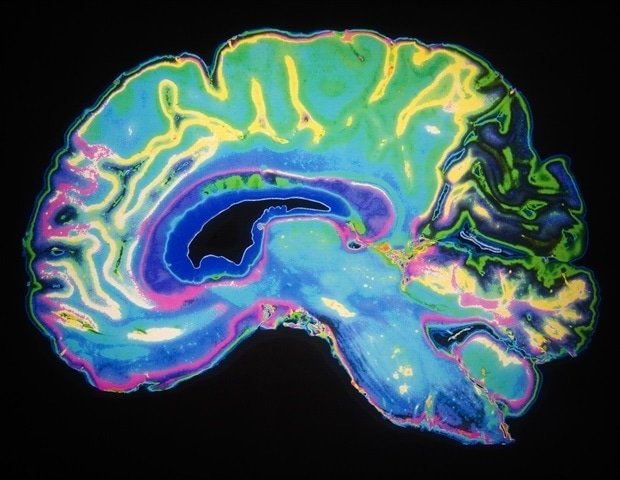

This study identified distinct but complementary brain markers. A combination of physical exposures (increased pollution, extreme temperatures, and lack of green space) was primarily associated with structural aging of the brain, particularly affecting areas central to memory, emotional regulation, and autonomic function. These structural changes are consistent with mechanisms such as neuroinflammation, oxidative stress, and vascular dysfunction, all of which may contribute to tissue degeneration.

In contrast, social factors such as poverty, inequality, and lack of support can have strong effects on brain aging. These pressures are associated with accelerated aging of brain regions that control thinking, emotion, and social behavior.